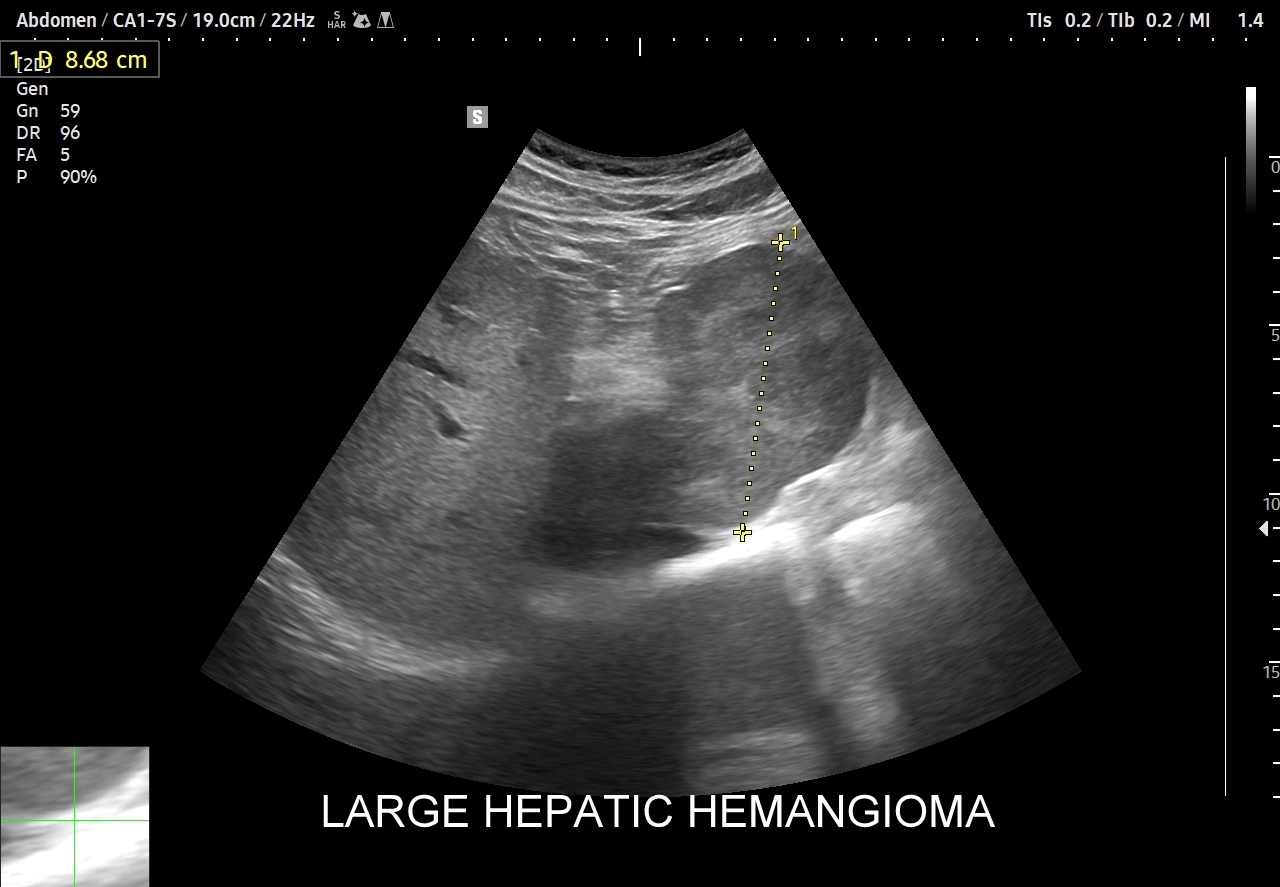

Naczyniaki duże, tj. powyżej 2-3 cm, mogą mieć strukturę niejednorodną echogenicznie, w tym obszary hypoechogenne. Spotyka się także naczyniaki o charakterystyce normo- lub hypechogenicznej, w szczególności w wątrobie stłuszczonej. Z powyższych względów należy mieć na uwadze i zapamiętać, że badanie USG w podstawowym trybie B nie jest wystarczające do postawienia rozpoznania naczyniaka wątroby. W ramach obrazowej diagnostyki różnicowej najbardziej pomocnym jest badanie USG z kontrastem (CEUS), w którym to naczyniak wątroby posiada charakterystyczny wzorzec wypełnienia.

W przypadku dużych naczyniaków obszary, które uległy wykrzepianiu pozostają awaskularne przez wszystkie fazy badania CEUS, tj. nie wypełniają się kontrastem (nonenhancing). W przeciwieństwie do powyższego konstelacja, w której to w fazie wczesnej pojawia się wzmocnienie, a następnie w fazie wrotnej lub późnej ulega wypłukaniu (hypoenhancement) świadczy o cechach złośliwych diagnozowanej zmiany ogniskowej w wątrobie i wyklucza rozpoznanie naczyniaka.